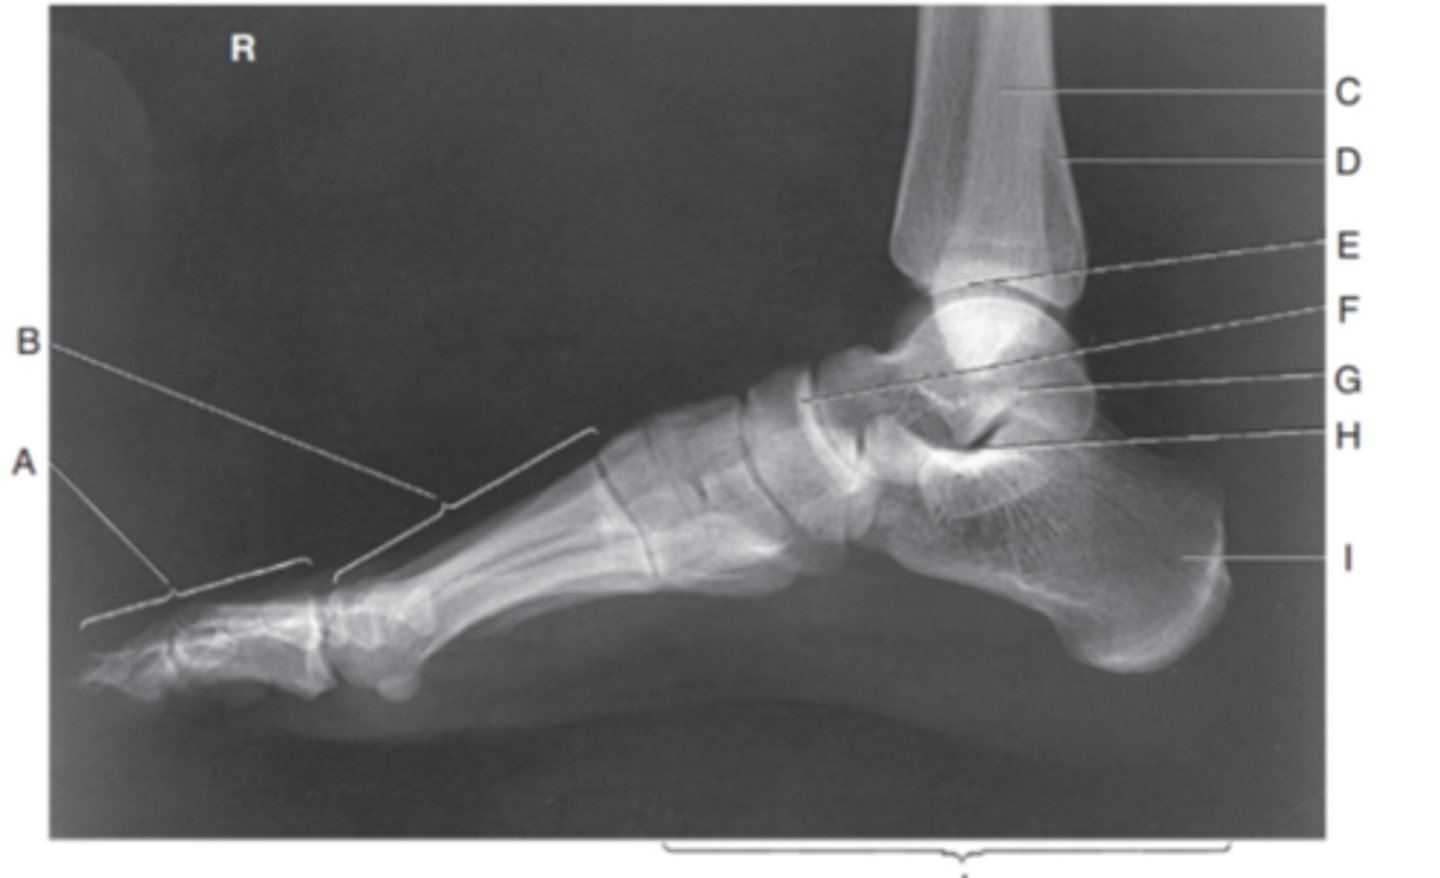

(LATERAL FOOT) what is A?

phalanges

what is B?

metatarsals

what is C?

fibula

what is D?

tibia

what is E?

Tibiotalar joint (mortise joint)

what is F?

navicular

what is G?

talus

what is H?

sinud tarsi

what is I?

calcaneous

what is J?

tarsals